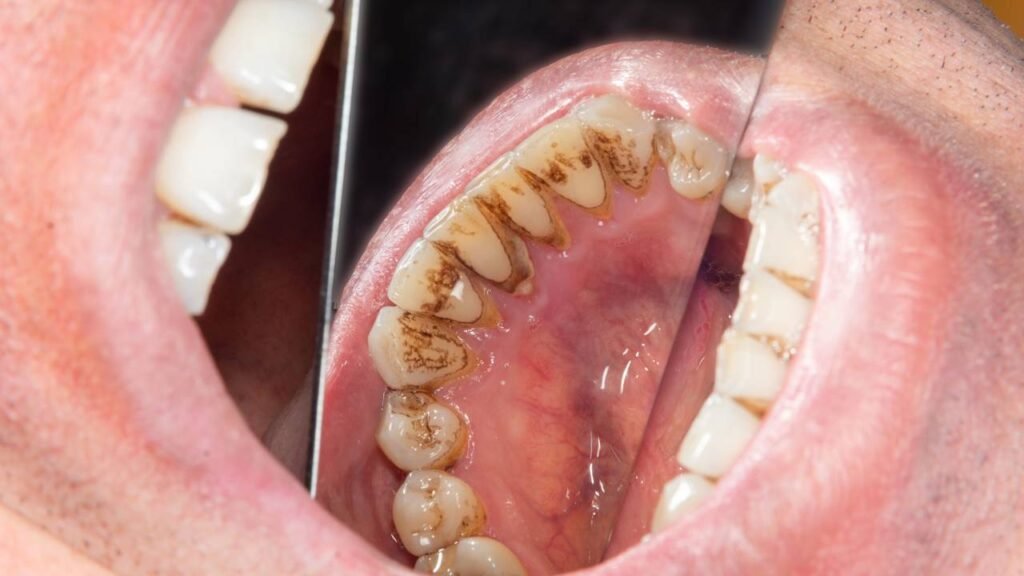

A palavra-chave central aqui é tártaro dental, termo usado para definir a placa bacteriana que se calcificou sobre os dentes. Esse material endurecido adere com força ao esmalte e ao contorno gengival, criando uma superfície irregular que favorece ainda mais a retenção de novas bactérias.

Em muitos casos, o tártaro se acumula não apenas na parte visível dos dentes, mas também abaixo da linha da gengiva, onde o acesso da escova é menor. Esse cenário favorece inflamação gengival, mau hálito persistente e, em fases avançadas, retração da gengiva e perda de suporte ósseo.

Quando a placa não é removida com fio dental e escovação adequados, minerais presentes na saliva, como cálcio e fosfato, passam a se depositar sobre essa estrutura. O resultado é uma camada endurecida, amarelada ou acastanhada, perceptível principalmente na região próxima às gengivas e na parte interna dos dentes inferiores.